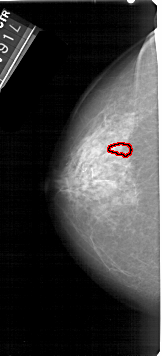

A_1706_1.RIGHT_MLO

RIGHT_MLO LINES 5176 PIXELS_PER_LINE 2671 BITS_PER_PIXEL 12 RESOLUTION 43.5 NON_OVERLAY

FILE: A_1706_1.LEFT_CC.OVERLAY

TOTAL_ABNORMALITIES 1

ABNORMALITY 1

LESION_TYPE CALCIFICATION TYPE PLEOMORPHIC DISTRIBUTION CLUSTERED

ASSESSMENT 4

SUBTLETY 1

PATHOLOGY BENIGN

TOTAL_OUTLINES 1

BOUNDARY